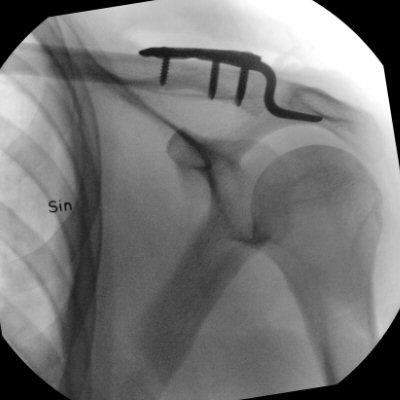

Luxerad AC-led Rockwood III dislocerad ca 22 mm. Opererad med hook-platta som togs bort 4 månader senare